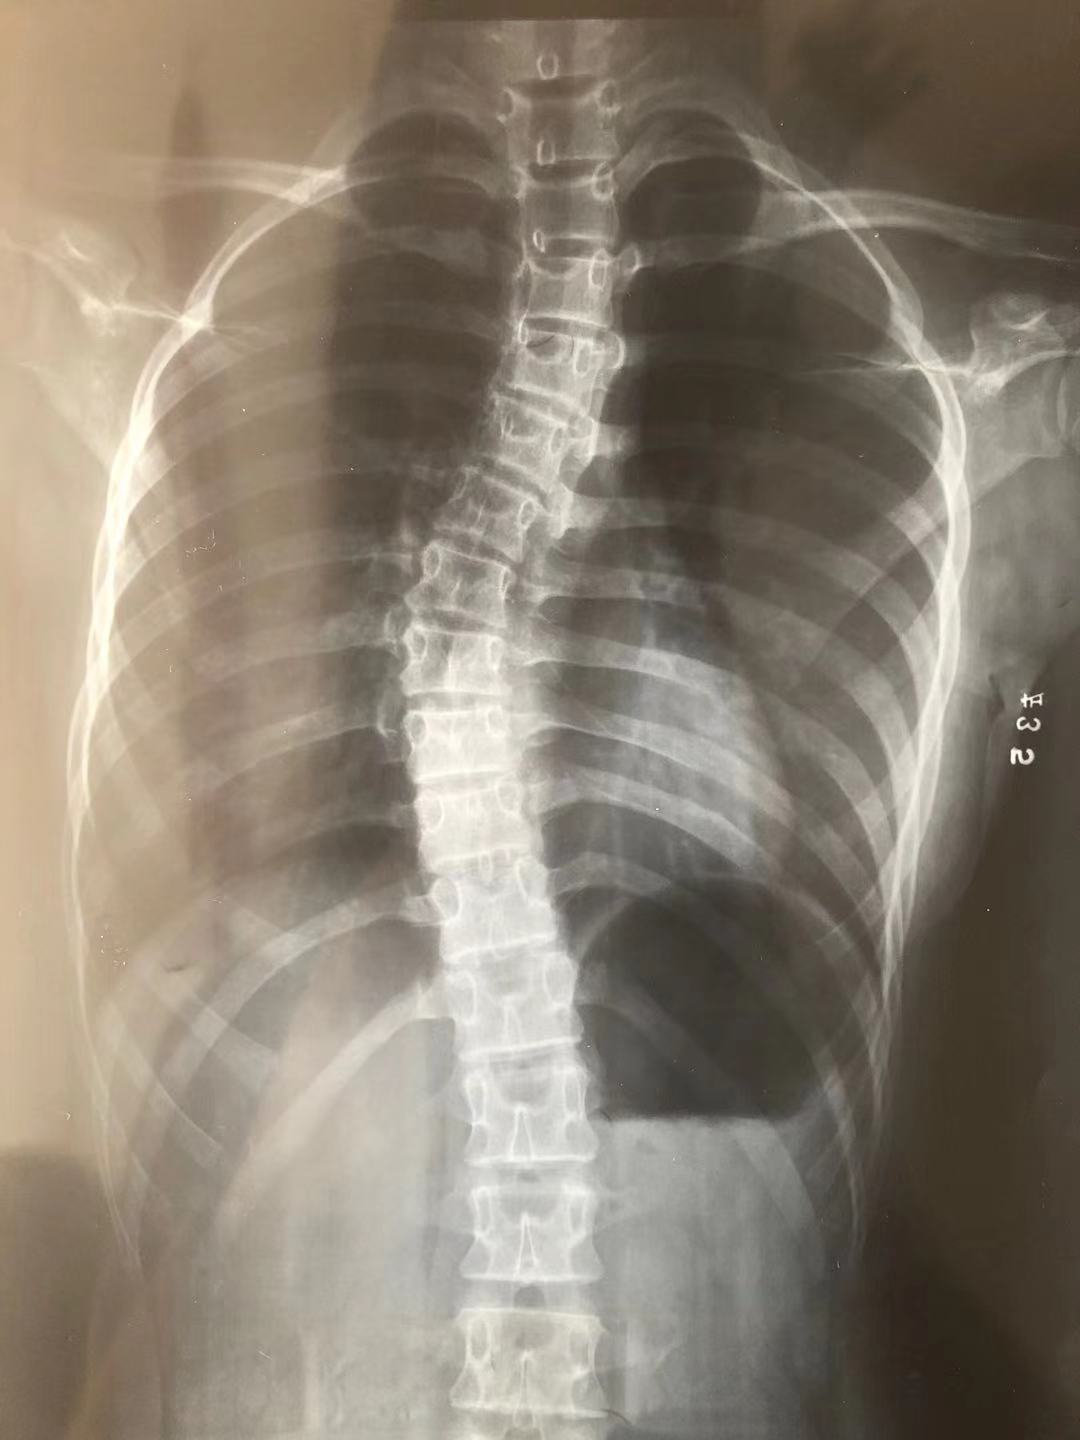

得出诊断之前,家里人都没有想过这么严重。我还记得那张确诊的 X 线里,胸椎、腰椎明显弯曲,还有旋转。

我的脊柱在黑白颜色中,扭曲出的 S 型异常明显,像极了诱惑亚当吃下厄运苹果的那条蛇。

图片来源:作者提供